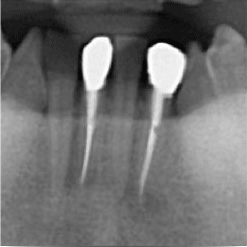

当院で処置した症例をご紹介します。

他院で抜歯と言われてしまった歯でも抜歯せずに対処した症例も多数あります。

黒い影が出ている部分が問題の個所で(根尖病巣)、治療後はこの影がなくなっているのが見て取れると思います。

保険適用。根尖病巣を治療した症例。リスクとして、稀ではありますが再発することがあります。